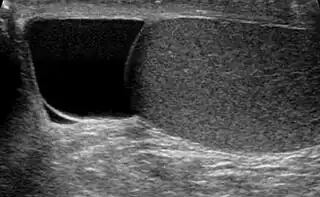

Hallado indoloramente, la masa quística en la cabeza del epidídimo, con diafanoscopia se ve claramente diferenciado del testículo, y es generalmente suficiente. Si existe incerteza, la ultrasonografía de escroto puede confirmar si es espermatocele.